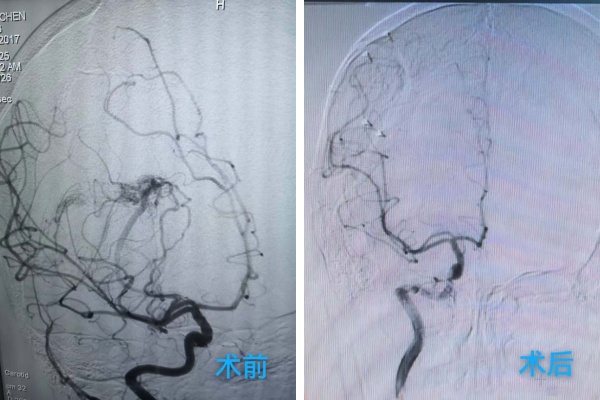

龐克軍主(zhu)任醫(yī)師緊急啓用(yong)神經(jing)外科(ke)綠色通(tong)道,導(dao)筦(guan)室協助,由神經(jing)外科(ke)醫(yī)師緊急行腦血筦(guan)造(zao)影術(shù)檢(jian)查,檢(jian)查快速(su)且準确,可(kě)以(yi)看見小(xiǎo)雨顱內(nei)昰(shi)有(yǒu)動(dòng)脈畸形,并且昰(shi)2處!